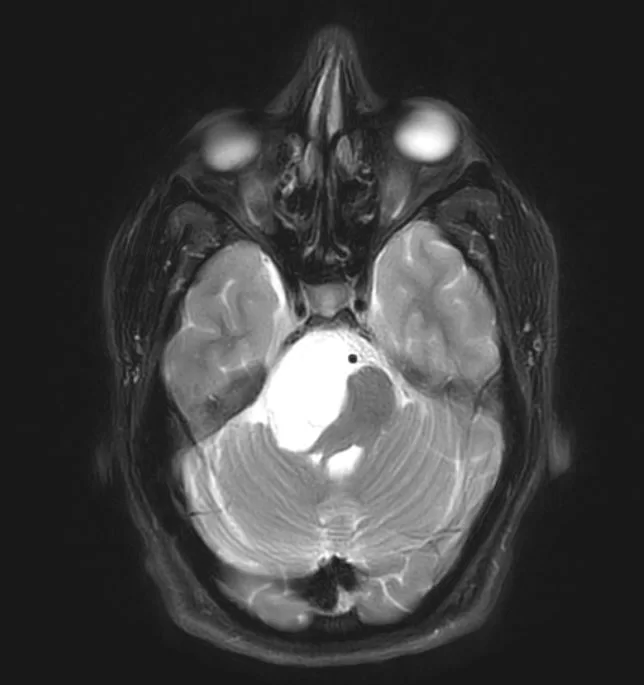

Επιδερμοειδής όγκος δεξιάς γεφυροπαρεγκεφαλιδικής γωνίας

Ασθενής 19 ετών με γνωστή χωροκατακτητική εξεργασία (επιδερμοειδες γεφυροπαρεγκεφαλιδικής γωνίας δεξιά) με προοδευτικά σημαντική αύξηση μεγέθους. Νευρολογικά ακέραιος. Ο απεικονιστικός έλεγχος με μαγνητική τομογραφία ανέδειξε